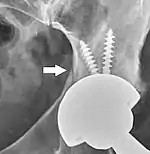

On radiography, it is normal to see thin radiolucent areas of less than 2 mm around hip prosthesis components, or between a cement mantle and bone. These may indicate loosening of the prosthesis if they are new or changing, while areas greater than 2 mm may be harmless if they are stable.[31] The most important prognostic factors of cemented cups are absence of radiolucent lines in DeLee and Charnley zone I, as well as adequate cement mantle thickness.[32] In the first year after insertion of uncemented femoral stems, it is normal to have mild subsidence (less than 10 mm).[31] The direct anterior approach has been shown to itself be a risk factor for early femoral component loosening.[33][34][35]